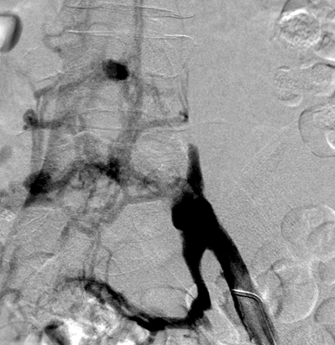

Vista de posición decúbito prono de trombo agudo en la vena femoral común izquierda y ausencia de flujo en las venas ilíacas.

Vista de posición decúbito prono de la pierna izquierda tras la trombectomía mediante el catéter DVX de AngioJet utilizando la técnica Rapid Lysis (25 mg de tPa en 250 cc de solución salina natural). Desaparición del trombo, oclusión subyacente de la vena ilíaca común izquierda revelada.

Primer plano de los stents.

El angiograma tras completar el procedimiento revela un rápido flujo a la VCI tras la inyección en la vena femoral.

Gerard O’Sullivan, University College Hospital, Galway, Irlanda (2009)